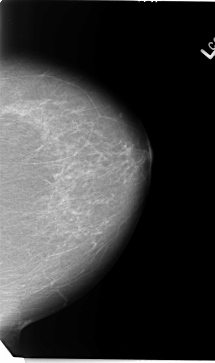

B_3090_1.LEFT_MLO

LEFT_MLO LINES 5792 PIXELS_PER_LINE 3632 BITS_PER_PIXEL 12 RESOLUTION 50 NON_OVERLAY